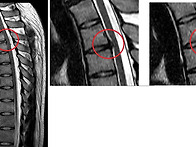

살고싶다 님의 흉추부위 ..

엔젤 26.02.02첫번째 사진은 수술후 전체적인 사진입니다.두번째는 해당부위 수술..